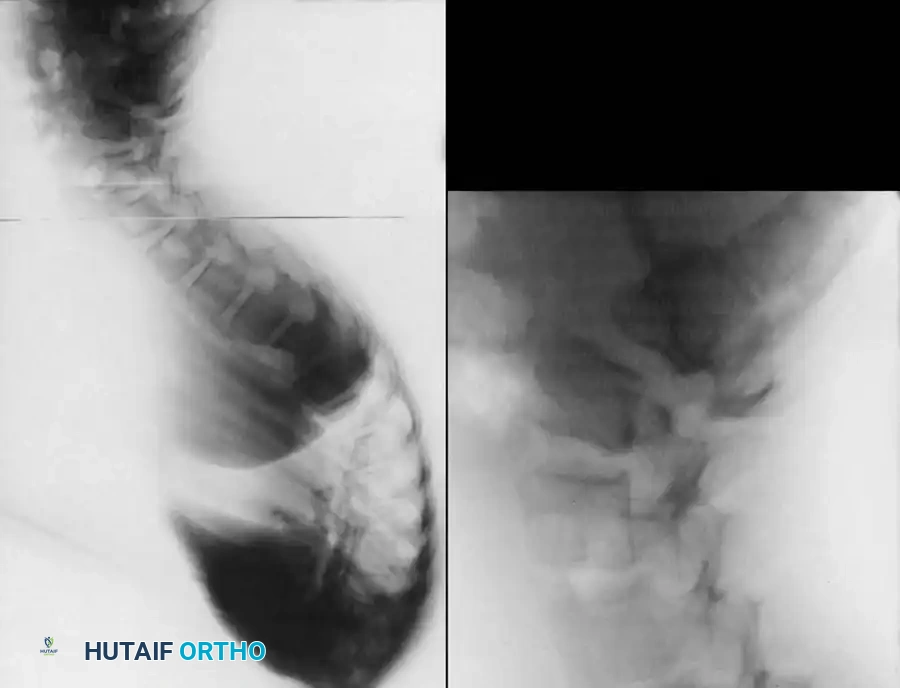

Rigid Scheuermann kyphosis failing to correct on prone extension.

Clinical presentation of severe thoracic kyphosis.

Clinical presentation demonstrating compensatory lumbar hyperlordosis.

Lateral radiograph demonstrating classic Scheuermann kyphosis with severe anterior wedging and Schmorl nodes.

Preoperative lateral radiograph highlighting the rigid structural curve.

Detailed view of apical vertebral wedging and endplate destruction.

A lateral radiograph taken with the patient hyperextended over a bolster is critical to assess the flexibility of the curve and to aid in preoperative planning.